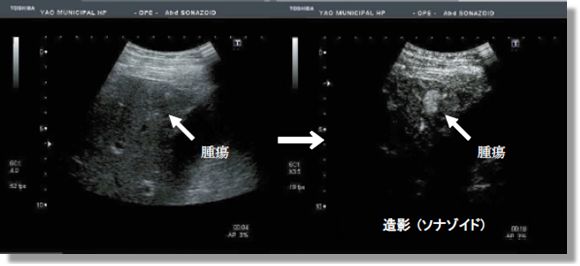

腹部エコー

肝臓・胆嚢・膵臓・腎臓・脾臓・消化管が観察対象となっており、腫瘍をはじめ、脂肪肝や胆石、膵炎、腎結石、虫垂炎および腸炎などを観察することが可能です。また、悪性腫瘍の判別や治療効果の判定に有用な造影エコーも行っています。検査時間は10分~20 分程度です。基本的には検査6 時間前からの絶食が必要な検査です。